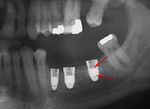

قبل زراعة الأسنان، يطلب من المريض اجراء فحص تصوير للأسنان، وعادة يطلب اجراء صورة خاصة (صورة أشعة بانوراما للأسنان) أو حتى فحص التصوير المقطعي المحوسب (CT)، للكشف والتشخيص عن حالات الأسنان التي ليس بالامكان رؤيتها من خلال الفحص الاعتيادي.

صورة شعاعية لغرسة السن.